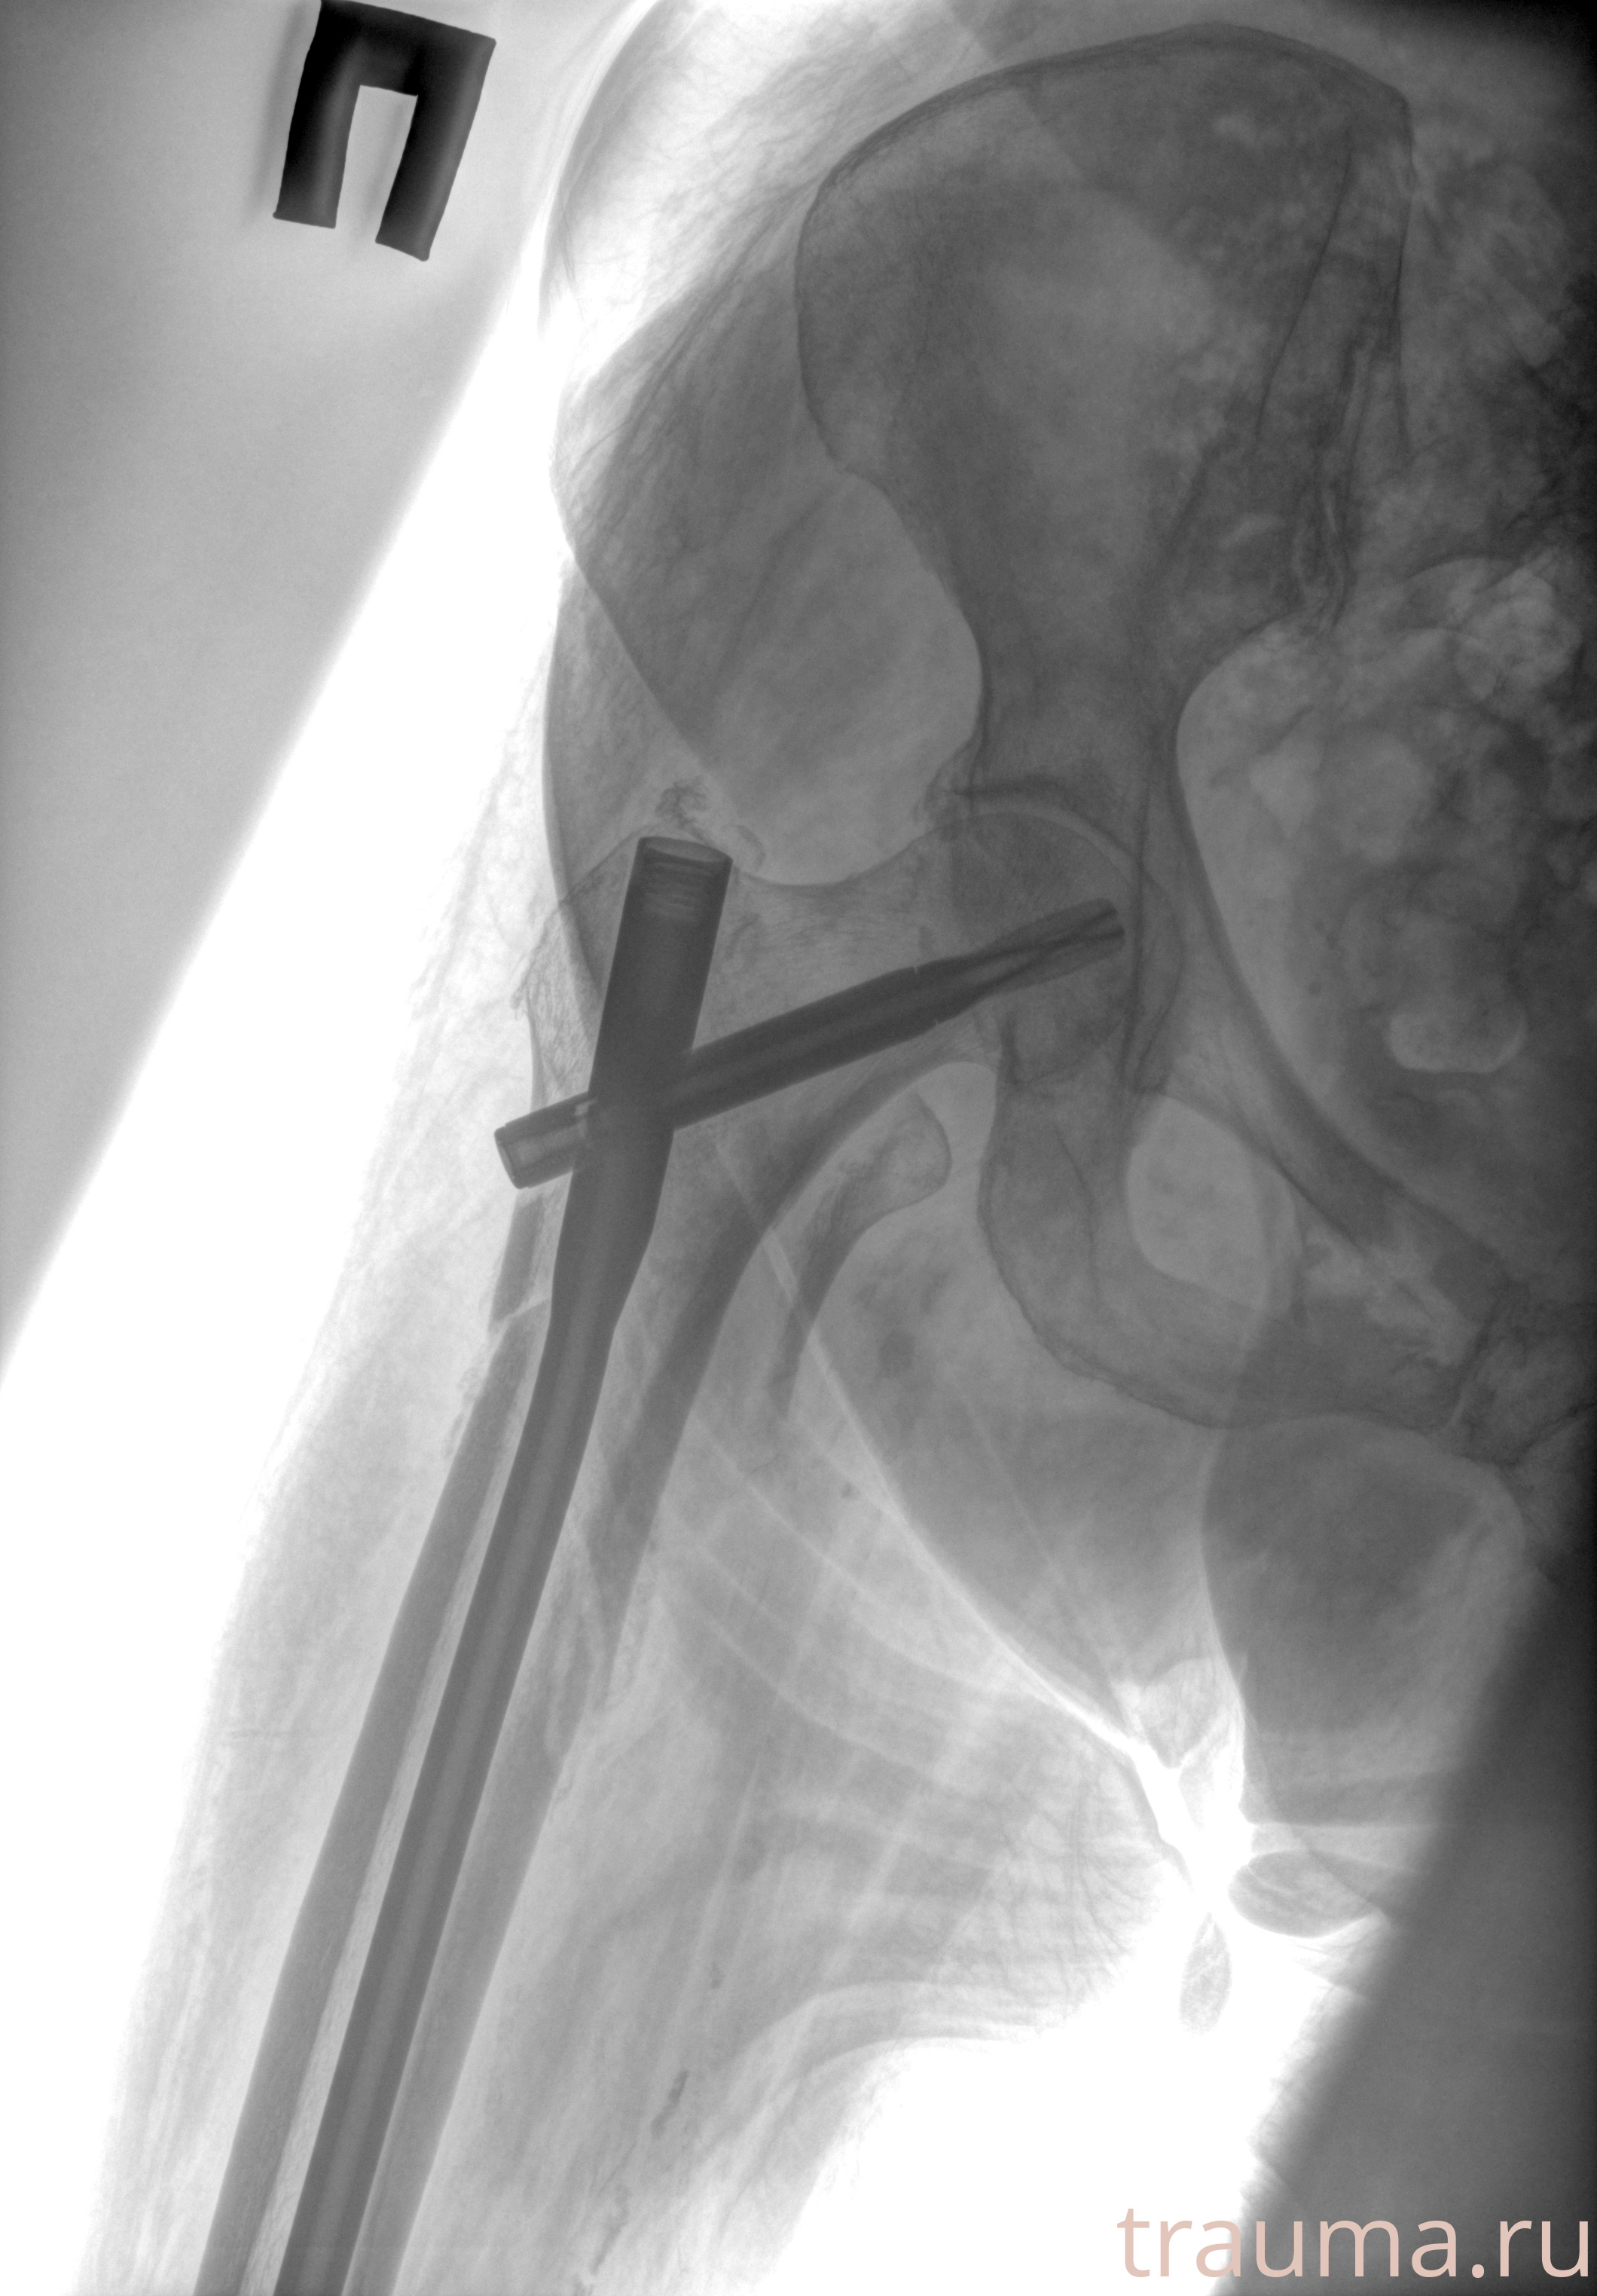

Рентген на дому: по вашему адресу приезжает врач-рентгенолог, травматолог-ортопед с мобильным рентгеновским аппаратом, проводит диагностику травмы или заболевания, делает необходимые рентгенограммы, дает рекомендации по дальнейшему лечению. Получить качественные снимки в домашних условиях возможно благодаря уникальной методике, разработанной МосРентген Центром для института  Склифосовского